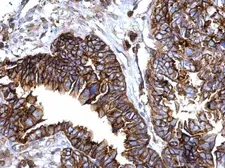

Images

Applications